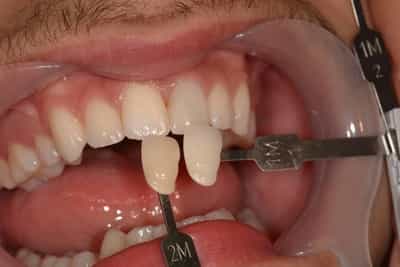

Première séance : Le praticien effectue une préparation pelliculaire sur la face externe des dents du patient, en retirant seulement une infime couche d’émail (de 0,2 à 0,5 mm). L’intervention est indolore.Une empreinte des dents préparées est prise et envoyée au laboratoire avec les instructions pour la teinte et la forme souhaitées.

Deuxième séance : Les facettes céramiques élaborées quelques jours après sont essayées puis collées sur l’émail des dents. Le praticien pourra jouer, à ce moment encore, sur la teinte en utilisant des résines de collage plus ou moins claires.